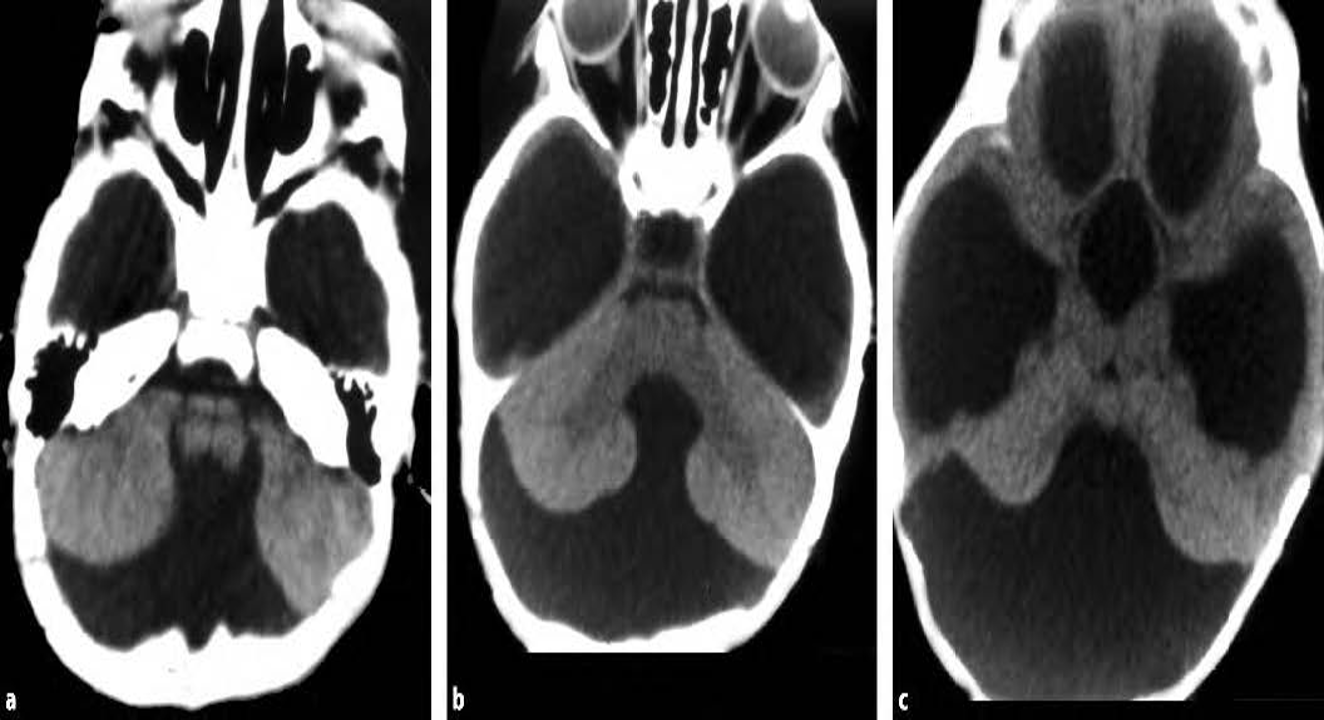

Absent cerebellar vermis. Large posterior fossa cyst communicating with fourth ventricle. Third ventricle, frontal and temporal horns of lateral ventricles are dilated.